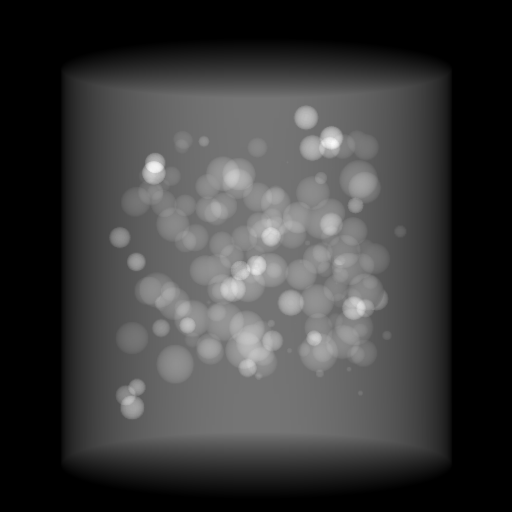

Refer to caption

(a) Orthogonal 0superscript00^{\circ}

(b) Perspective 0superscript00^{\circ}

(c) Perspective deformation ((b)-(a))

(d) Perspective 180superscript180180^{\circ}

(e) Difference of Perspective 0superscript00^{\circ} and 180superscript180180^{\circ}

(f) RGB 0superscript00^{\circ} and 180superscript180180^{\circ}

Figure 6: An example for perspective deformation learning from dual complementary views: (a) the orthogonal projection of the 3D bead phantom from the 0superscript00^{\circ} view; (b) the perspective projection from the 0superscript00^{\circ} view; (c) the difference image between (b) and (a); (d) the perspective projection from the 180superscript180180^{\circ} view; (e) the difference image between (d) and (b); (f) the RGB stack of the 0superscript00^{\circ} and 180superscript180180^{\circ} perspective projection images, where the magenta and green areas correspond to the positive (bright) and negative (dark) areas in (e). The intensity range [0, 11] is converted to [0, 255] for visualization.

Note that when and only when z=0𝑧0z=0, which is m=m=1superscript𝑚𝑚1m^{\prime}=m=1, d180subscript𝑑superscript180d_{180^{\circ}} and dPDsubscript𝑑PDd_{\text{PD}} both equal to 0. This provides a practical way to observe which structures suffer from perspective deformation by assessing deviations between the two complementary views.

The orthogonal and perspective projection images of the same 3D bead phantom in a complementary view setting are displayed in Fig. 6. Fig. 6(c) shows the perspective deformation, which is the difference between the perspective projection (Fig. 6(b)) and the orthogonal projection (Fig. 6(a)) from the 0superscript00^{\circ} view. Fig. 6(c) clearly demonstrates that the magnitude of perspective deformation increases from the center outwards radially. The 180superscript180180^{\circ} perspective projection image is displayed in Fig. 6(d) and its difference with respect to the 0superscript00^{\circ} perspective projection is displayed in Fig. 6(e). Fig. 6(e) is similar to Fig. 6(c) in bead areas, which illustrates that the deviation between two complementary views has strong correlation to perspective deformation. To integrate such dual-view information, like Fig. 5(d), we convert the perspective projections images from the 0superscript00^{\circ} and 180superscript180180^{\circ} views to a 3-channel RGB image in Fig. 6(f). The red and blue channels use images from the 0superscript00^{\circ} view, while the green channel uses images from the 180superscript180180^{\circ} view. In the RGB images, the color reveals the intensity difference between the 0superscript00^{\circ} and 180superscript180180^{\circ} perspective projection images. Grey areas contain close intensity values from both views. Instead, magenta and green areas indicate larger intensity values from the 0superscript00^{\circ} and 180superscript180180^{\circ} views respectively, where perspective deformation correction is necessary. They correspond to the positive (bright) and negative (dark) areas in the difference image in Fig. 6(e). In Fig. 6(f), the magenta beads and their corresponding green beads are located close to each other, which allows a network with limited receptive field size to capture bead-to-bead (point-to-point) dependency.